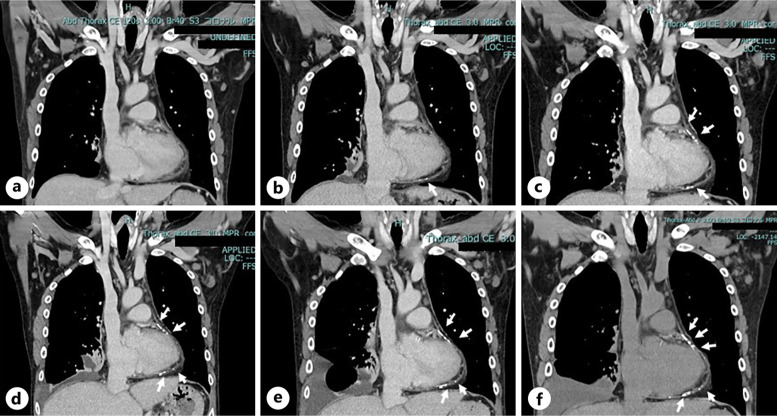

Case presentation: We report the case of a 53-year-old man on hemodialysis who developed CP with shock. His blood pressure was 55/30 mm Hg at the time of hospitalization due to presyncope. He continued hemodialysis but with some difficulty. However, right pleural effusion persisted because of impaired fluid removal by hemodialysis. Despite such severe manifestations, the distinctive clinical features of CP were lacking. By carefully evaluating the time course of computed tomography images, progressive calcification in the pericardium emerged as a significant clue. Cardiac catheterization subsequently revealed a dip-and-plateau pattern of right ventricular pressure, which led to a definitive diagnosis of CP. Soon after the diagnosis, he underwent successful surgery.

Conclusion: An important finding was that, unlike calcific lesions in the general dialysis population, the patient's calcific lesions were mostly confined to the pericardium and progressed on a monthly basis. Thus, the present case may provide deep insight into the diagnosis of CP and the management of hemodialysis patients with severe hypotension.